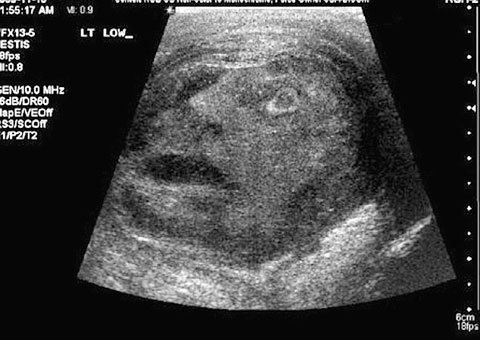

Các bác sĩ đă hết sức sửng sốt khi phát hiện một khuôn mặt quỷ qua màn h́nh khi siêu âm một khối u tinh hoàn.

Một người đàn ông 45 tuổi đă đi khám sau khi cảm thấy đau tinh hoàn. Trong quá tŕnh siêu âm, các bác sĩ phụ trách đă phải giật ḿnh khi thấy một gương mặt quỷ trên màn h́nh, ngay trong khối u tinh hoàn của bệnh nhân này. Tiến sĩ Greg Roberts và Tiến sĩ Naji Touma đến từ Trường đại học Queen (ở Ontario, Canada) đă gửi h́nh ảnh kinh ngạc này cho một tạp chí sức khỏe liên quan đến tiết niệu. Trong bức ảnh là một khuôn mặt ma quái với chiếc mồm há rộng, mắt mở to nh́n chằm chằm lên màn h́nh, vẻ sợ hăi.

Khuôn mặt quỷ qua màn h́nh khi siêu âm khối u tinh hoàn (Ảnh: Daily Mail)

Sau cuộc thảo luận xem liệu đây có phải là một dấu hiệu từ một vị thần hay thiên chúa nào không, các bác sĩ đă kết luận, đó chỉ là một trường hợp xảy ra ngẫu nhiên và hy hữu. Các chỉ số siêu âm cho thấy, bệnh nhân này bị viêm tinh hoàn nặng. Các bác sĩ cũng đo được một lượng hormone cao bất thường, dấu hiệu cho thấy bệnh nhân này đang trong quá tŕnh chuyển bệnh ung thư. Bệnh nhân nam này sau đó đă được cắt bỏ khối u trong tinh hoàn.